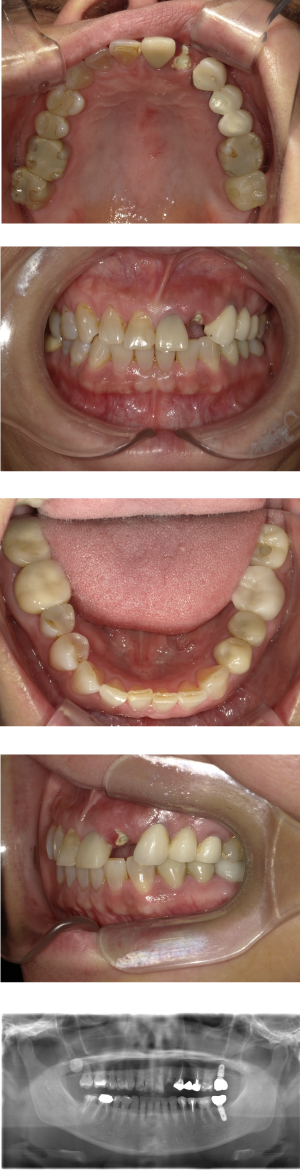

30代 女性 奥歯 インプラント

| 年代・性別 | 30代・女性 |

| 治療回数 | 10回(術前治療・検査除く) |

| 治療期間 | 約1年 |

| 料金 | ¥410,300(税込)※別途検査料 |

失った歯を補うために、インプラント治療は優れた治療方法です。 しかし、全ての人にインプラント治療が優れている治療ではありません。 |

| 副作用 | 術後に腫れ・痛みが出る可能性がある。 |